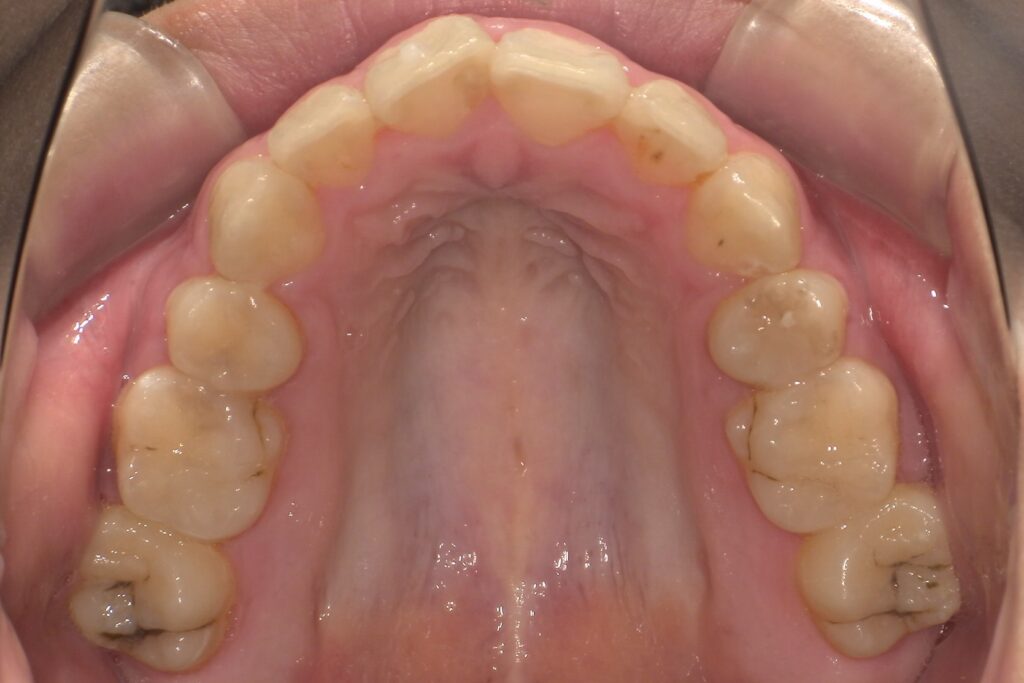

歯が少しだけズレてきた、隙間が開いてきた↓

見た目が気になる、前歯中心の後戻り↓

軽度な後戻り(前歯の傾き・隙間)

1~3mm程度のズレやすき間

例:前歯が少しねじれた/すき間が空いた

中等度の後戻り(複数の歯のズレ)

上下の歯並びが少しガタついてきた